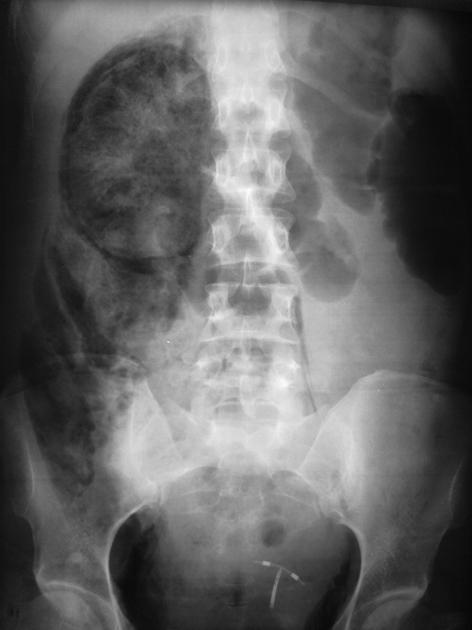

3 days

Diabetic patient with right flank pain, fever, dysuria and leukocytosis. What does the Xray show? image from https://t.co/b9iFiqs7bv